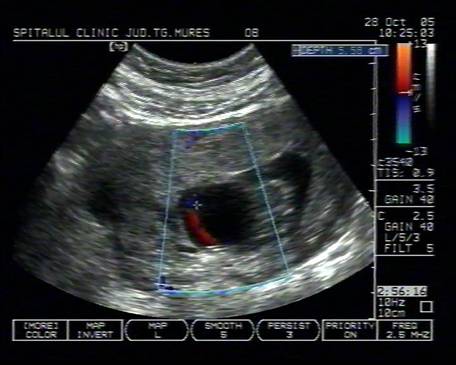

Fig. nr.108. Sarcina 7 saptamani la ecografia abdominala.

Fig. nr.126 Acelasi fat ca in figura precedenta, sectiune transversala abdominala, cu ecou Doppler la periferia omfalocelului